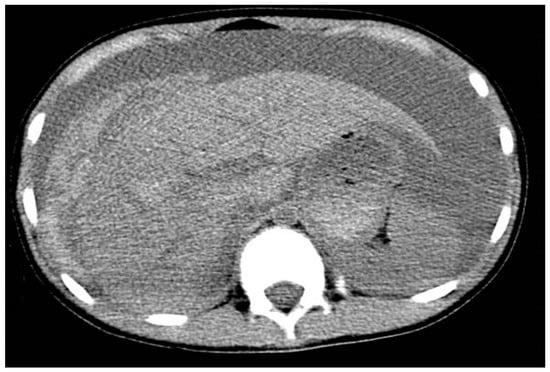

- Zakaria, O.M.; Daoud, M.Y.I.; Zakaria, H.M.; Al Naim, A.; Al Bshr, F.A.; Al Arfaj, H.; Al Abdulqader, A.A.; Al Mulhim, K.N.; Buhalim, M.A.; Al Moslem, A.R.; et al. Management of pediatric blunt abdominal trauma with split liver or spleen injuries: A retrospective study. Pediatr. Surg. Int. 2023, 39, 106. [Google Scholar] [CrossRef]